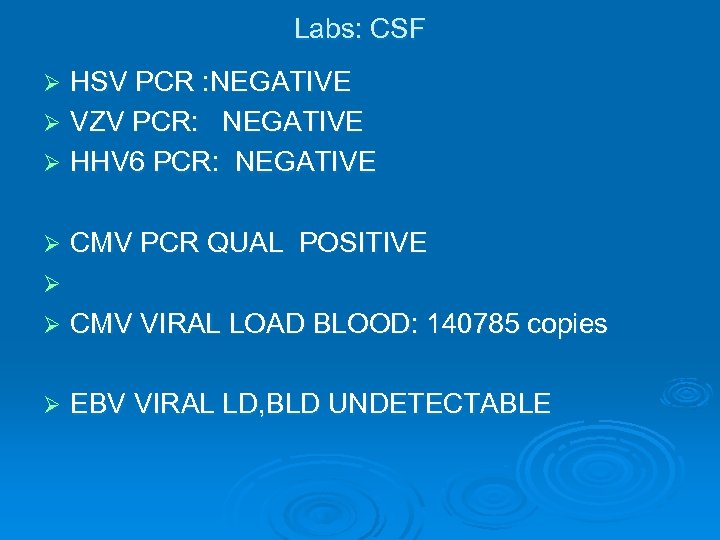

Labs: CSF HSV PCR : NEGATIVE Ø VZV PCR: NEGATIVE Ø HHV 6 PCR: NEGATIVE Ø Ø CMV PCR QUAL POSITIVE Ø Ø CMV VIRAL LOAD BLOOD: 140785 copies Ø EBV VIRAL LD, BLD UNDETECTABLE